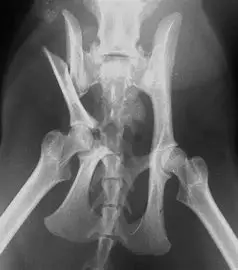

Les fractures du bassin sont des lésions complexes et graves, souvent résultant de traumatismes à haute énergie, tels que des accidents de la voie publique ou des chutes de grande hauteur. Elles nécessitent une prise en charge rapide et une évaluation précise pour optimiser la récupération fonctionnelle des patients et réduire les risques de complications. Parmi ces fractures, les disjonctions sacro-iliaques occupent une place particulière en raison de leur impact sur la stabilité de l’anneau pelvien et les défis qu’elles posent en termes de diagnostic et de traitement.

La disjonction sacro-iliaque est une lésion caractérisée par la séparation de l’articulation sacro-iliaque, un point clé de l’articulation entre le bassin et la colonne vertébrale. Elle peut survenir isolément ou en association avec d’autres fractures du bassin. Cette lésion entraîne une instabilité majeure du bassin, ce qui peut compromettre la fonction locomotrice du patient et causer des douleurs intenses. L’instabilité de l’anneau pelvien nécessite un traitement précis pour restaurer l’alignement anatomique et la stabilité, afin de prévenir les complications comme les douleurs chroniques, les troubles neurologiques ou une inégalité de longueur des membres inférieurs.

La disjonction sacro-iliaque pose un défi diagnostic important en raison de sa complexité anatomique. L’évaluation clinique seule ne suffit souvent pas à en déterminer la gravité et les implications. Les techniques d’imagerie jouent donc un rôle essentiel dans le diagnostic et le suivi de ces fractures.

L’imagerie médicale a considérablement évolué ces dernières années, permettant une meilleure visualisation des structures anatomiques complexes. Parmi les outils les plus avancés, la reconstruction en trois dimensions (3D) offre une compréhension détaillée de l’anatomie et des déplacements osseux, indispensable pour évaluer la sévérité des disjonctions sacro-iliaques.

Grâce à l’imagerie 3D, il est possible de modéliser avec précision les fractures et les disjonctions, permettant aux chirurgiens de planifier l’intervention chirurgicale de manière optimale. L’imagerie 3D offre plusieurs avantages :

À la Clinique La Bonne Patte, nous disposons de la technologie d’imagerie 3D, ce qui nous permet de prendre en charge les fractures du bassin, y compris les disjonctions sacro-iliaques les plus complexes. Cet équipement de pointe est un atout majeur pour nos équipes chirurgicales, offrant une précision inégalée dans le diagnostic et le traitement des fractures.